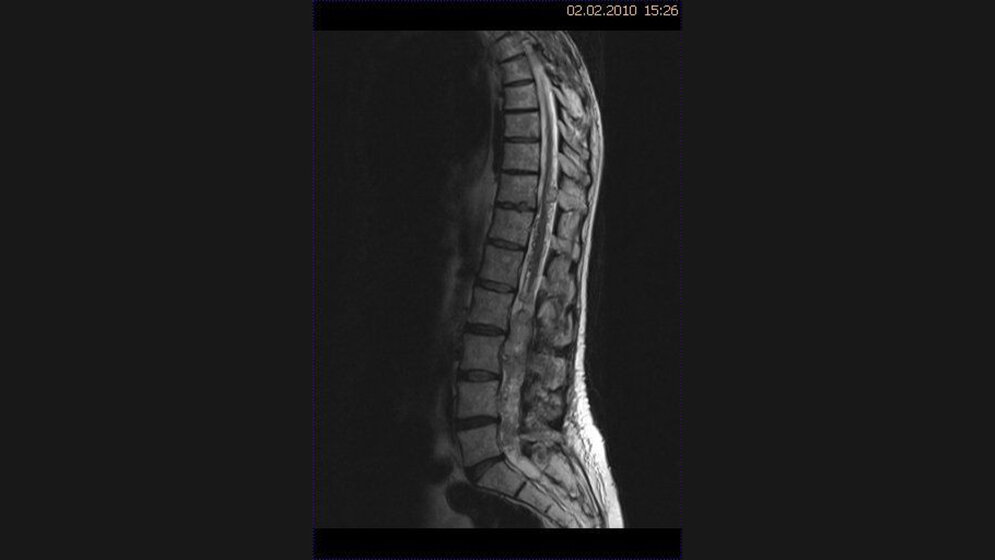

Tumoren des Spinalkanals und des Rückenmarks können erhebliche neurologische Probleme mit Parästhesien, sensomotorischen Defiziten sowie Darm- und Harnblasenstörungen verursachen und auch zur Letalität führen.

Intramedulläre Tumoren sind seltener als demyelinisierende Rückenmarkprozesse. Das MR-Bild der mangioblastome hängt von der Größe ab. Von Hämangioblastomen verursachte Blutungen in den Subarachnoidalraum oder das Hirngewebe sind sehr selten. In der KHBW-Region können zahlreiche Läsionen lokalisiert sein.